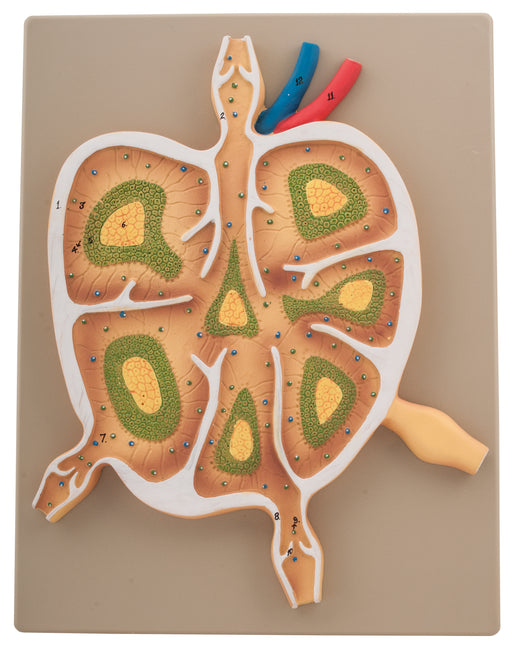

Lymph Node L.S.

This model showing semi-schematic presentation of the internal formation of a lymph node with the vessels leading to and from the node. Mounted on ...